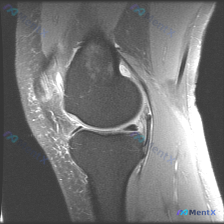

怀疑半月板异常但单张MRI没找到问题?来梳理这个膝关节病例的分析思路

最近碰到一个有意思的读片病例,患者临床提示半月板异常,但提供的单张MRI并没有看到明确问题,整理一下完整的分析思路给大家参考。

这是一份膝关节矢状位MRI扫描图像,临床问题是排查"半月板异常",我们先对影像做系统性评估:

- 影像基本信息:这是T2/质子密度加权矢状位图像,清晰显示股骨远端、胫骨近端、交叉韧带、半月板等解剖结构

- 系统性阅片结果:

- 骨皮质、骨髓:未见明显水肿或异常信号

- 关节软骨:轮廓光整,无明显剥脱缺损

- 半月板:本层面半月板形态呈典型楔形,内部无穿透关节面的高信号,无碎片化或移位

- 交叉韧带:前后交叉韧带走行连续,信号正常,无明显断裂或水肿

- 髌韧带、髌下脂肪垫:信号均匀,无异常

- 关节腔:无明显大量积液,滑膜无增生

- 周围软组织:未见明显肿块、囊肿或水肿